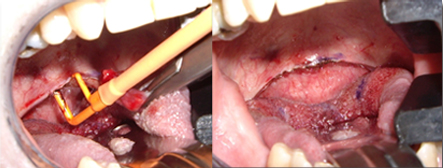

更佳的美容效果,更快的傷口愈合過程。

更適合于病理活檢的采集,取皮瓣做移植等。

適用于細(xì)微、精細(xì)的切割如頭頸部,敏感部位皮膚的切割。

可實(shí)現(xiàn)切割,凝血同步。

適合于皮下組織的切割和剝離。